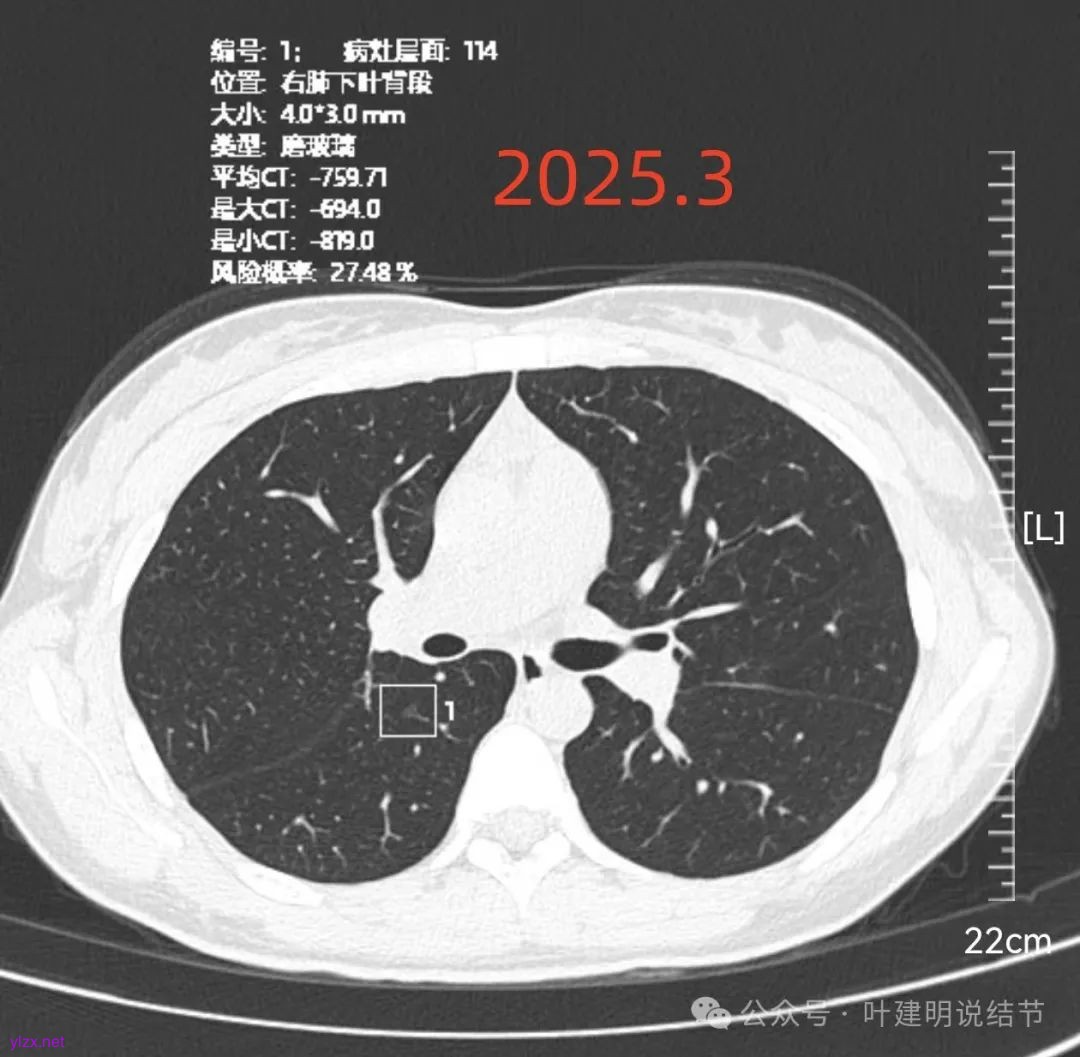

再看2025年3月的影像:

各病灶均无明显吸收好转,但显然也说不上有明显进展。所以基本上要考虑是肿瘤范畴的(包括肺泡上皮不典型增生或肺泡上皮增生)。但危险性显然不算高,至少近2年了没有什么进展,即使病灶6最厉害的也是纯磨密度伴空腔。